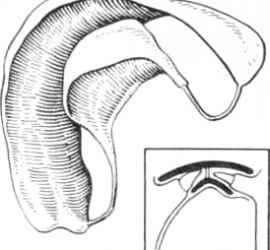

Реактивное тяжелое общее состояние организма, наступающее вскоре после травмы. Развивается в связи с нарушением нервной регуляции жизненных процессов и проявляется тяжелыми расстройствами гемодинамики, дыхания и обмена веществ. Этиология. Тяжелые ранения и повреждения, сопровождающиеся обширным размозжением тканей, ампутацией (отрыв) органов лица, массивными ушибами и сдавлениями челюстно- лицевой области, кровопотерей и кислородным […]